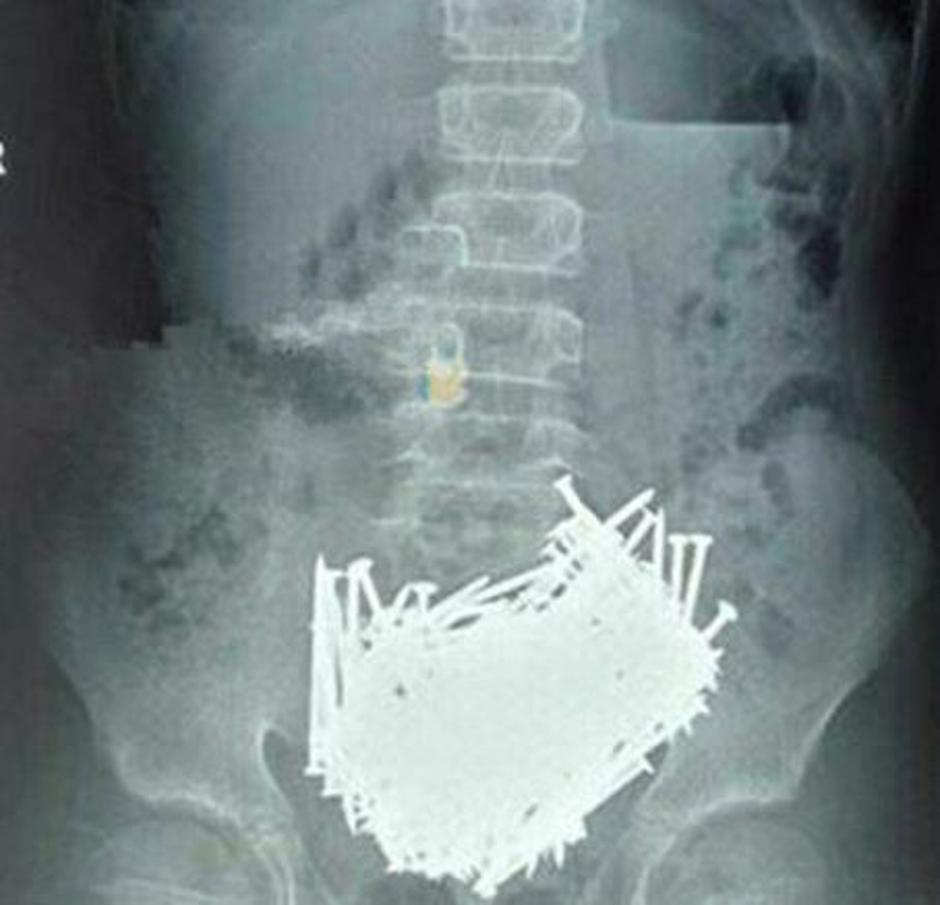

V želodcu 52-letnika iz Francije so našli na stotine kovinskih predmetov, vključno z noži, žeblji, izvijači in kovanci. Sicer je Francoz v zadnjih petih letih kar petkrat oobiskal nujno medicinsko pomoč, nazadnje pa so mu diagnosticirali psihozo. Pristal je v bolnišnici za duševne bolezni.

V trebuhu dva kilograma železa

Tudi osebje bolnišnice Sangei Gandhi v Indiji je doživelo šok. 35-letni Maksud Khan je imel v želodcu 263 kovancev, na ducate britvic, 15 centimetrov velik kos zarjavele železne skodelice, štiri velike igle, nekaj kosov stekla, v njegovem trebuhu pa so našteli tudi sto žebljev. V trebuhu moškega se je nabralo za dva kilograma železa.

Khanovi sorodniki so povedali, da je nesrečnik trpel zaradi hude depresije: "Kadarkoli je občutil potrebo po zaužitju kovanca, ga je pač pojedel in to tako, da ga je poplaknil z vodo," je dejal eden od družinskih članov.